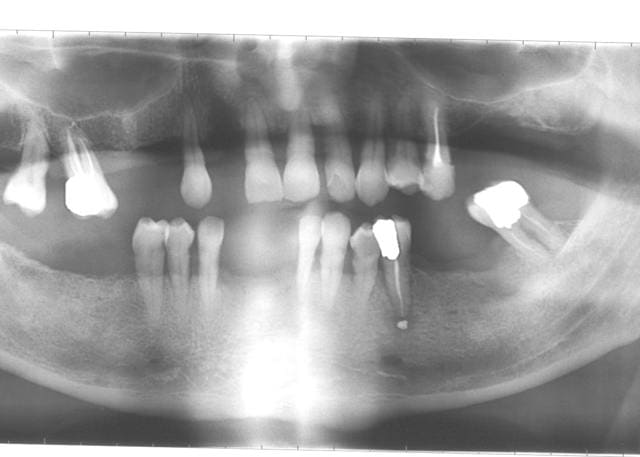

Que vas tu faire des molaires, et que ferait Phil,s'il me lit. Pour alhoun, c'est bon, je sais.

36 tentative de retraitement, les autres vont gicler je pense.

avec une bonne RTE, tu devrais pouvoir nous sauver la 35. Avec un peu de paro, peut être la 26.

Difficile de se prononcer pour le reste rien qu'avec une pano.

Par chance, il n'y a pas d'IC à démonter...

la 35 bien sûr on va essayer, mais la question était pour le molaires.

-extraction 16, 17, 26, 27, et 37.

-rtt 35 et 36.

-sinus gauche et droit, implants 16, 17, 26, 27 et 37.

mais le but du post c'est pas le plan de traitement, mais comment on peut laisser les patients en arriver là, et comment après trouver les mots pour leur annoncer les mauvaises nouvelles.